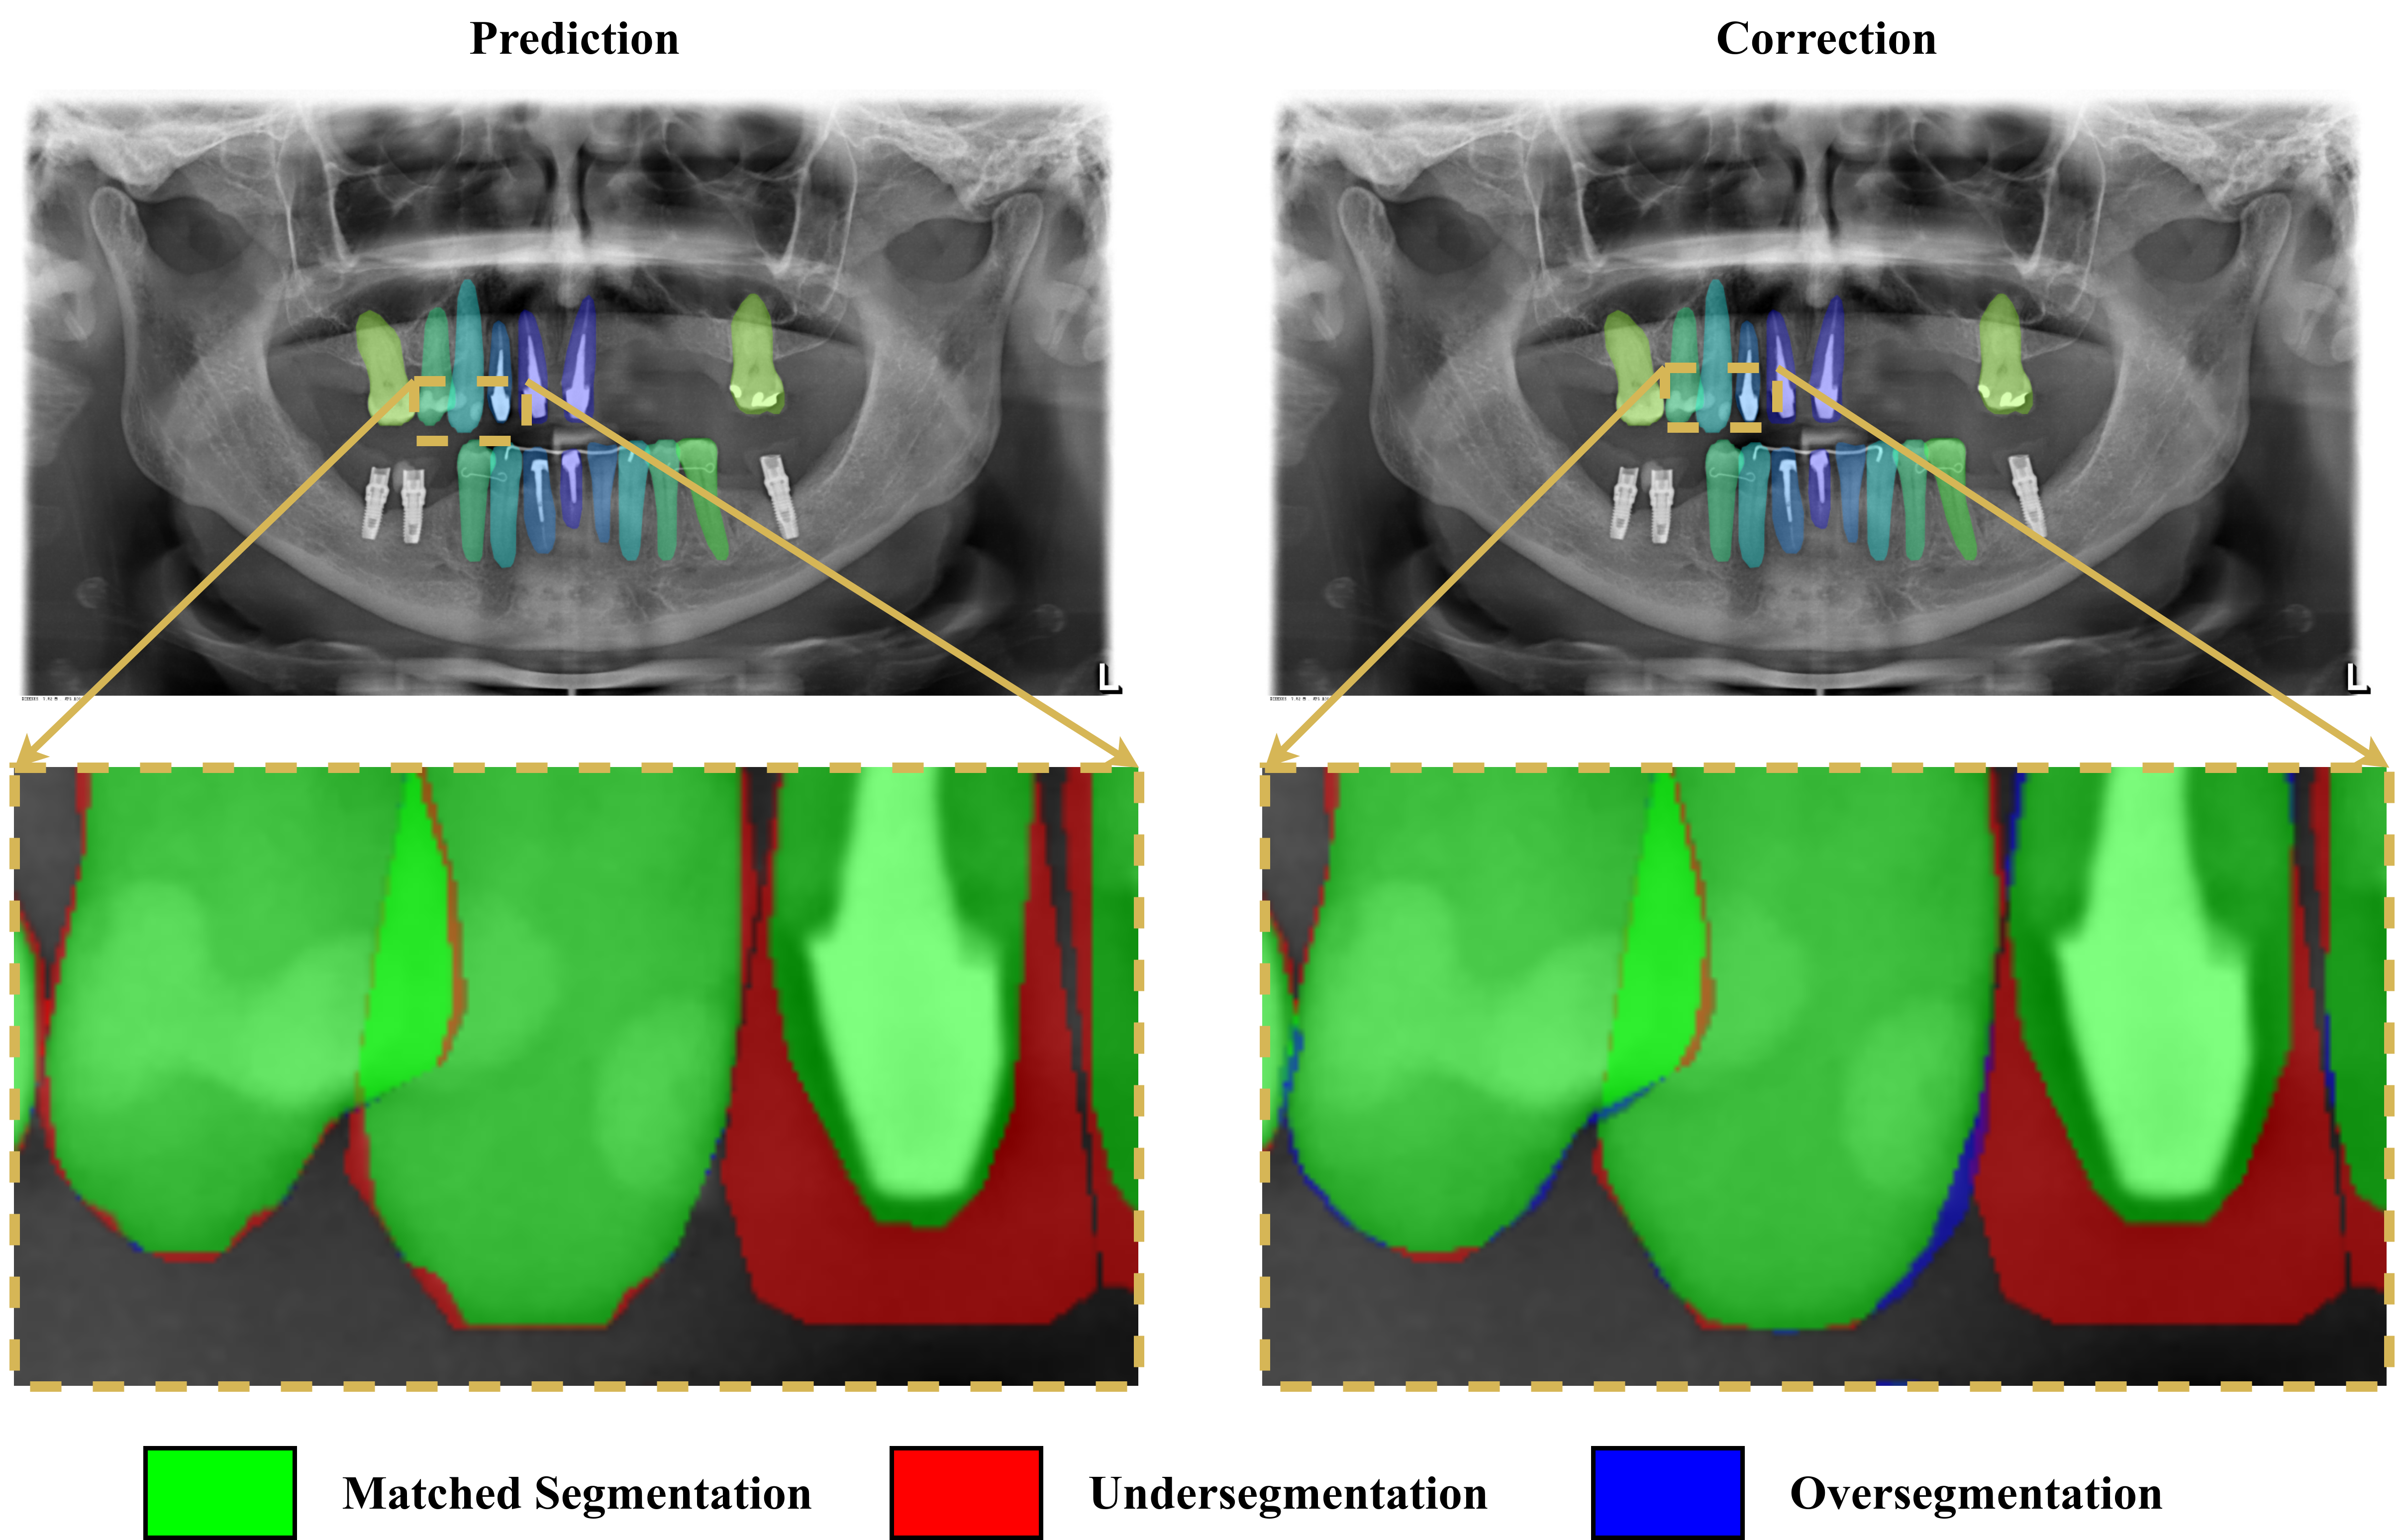

3.7 Qualitative analysis

The quantitative analyses guided our qualitative analyses. We focused on the best and worst results according to the primary metric, comparing the ground truth with the network predictions and the verified labels. Figures 12 (a) and (b) illustrate the best and the worst HTC 4’s results, respectively, according to the segmentation mAP on the test data set. Figure 12 (a) corresponds to a well-focused, crisp and clear radiograph from a 32-teeth healthy mouth, characteristics common to the best results. From the zoomed area, we see that the annotation correction led to a final label closer to the ground truth and also less noisy.

The worst result, illustrated in Figure 12 (b), came from a slightly blurry image from an unhealthy mouth, a common pattern in the radiographs of the worst results. However, in this case, the network performance was reasonably good, and the low metric was due to main factors. First and most important, the annotator wrongly labeled the teeth 32, 33, 34 and 35 respectively as teeth 31, 32, 33 and 34, probably due to a sequence of typos, which reduced the segmentation mAP significantly. Second, the presence of radiolucent material prostheses and restoration encumbered the segmentation task for both model and annotator. The zoomed area shows that model undersegmented those spots, which were adjusted by the annotator, but still missed some areas. The other annotation corrections smoothed the noisy borders and reduced the difference from the ground truth labels. We additionally illustrate in Figure 12 (c) a sample result on a mixed dentition mouth. These radiographs are challenging for models and human annotators due to overlapping. In this particular image, there are also occlusions between posterior teeth, hardening the task. However, the model prediction proved to be adequate, even before the labeling verification. The zoomed area shows that the corrections reduced the gap to the manual ground truth labels, but there were some divergences for root segmentation of teeth 54 and 55.

Refer to caption

(a) HTC 4’s best result, which happened on a well-focused, crisp and clear radiograph from a 32-teeth healthy mouth, characteristics common to the best results.

(b) HTC 4’s worst result, which happened on a slightly blurry radiograph from an unhealthy mouth with radiolucent material prostheses.

(a) Sample of HTC 4’s results on a mixed dentition radiograph.

Figure 12: HTC 4’s best and worst results according to the segmentation mAP on the test set, and an additional result sample on a mixed dentition radiograph. The illustrations compare the predictions before and after the corrections by the annotators. The zoomed areas highlight the matched segmentation, undersegmentation, and oversegmentation with the ground truth labels, evincing that the corrections led the final labels to be less noisy and closer to the ground truth.